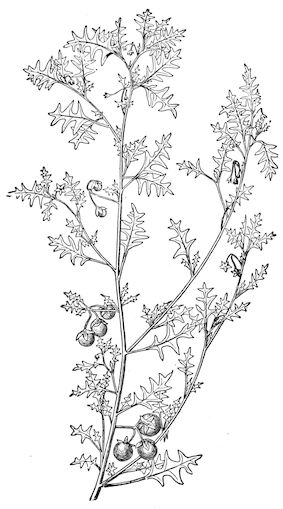

Fig. 8.—Transverse section through the middle region of the face in a pig suffering from osseous cachexia.

18In the final stages, the bones may be cut with a knife, and a time arrives when bony tissue seems completely to have disappeared; thus, as shown in Fig. 8 herewith, it was possible to cut the entire head of a pig into thin slices without the slightest difficulty. All parts of the head had been affected by the softening change.

From the chemical point of view, the diminution in mineral salts and in phosphate of calcium has long been recognised, but the degree of this change varies according to the phase. In human beings the proportions have been estimated as follows: Normal bone, 50 to 80 per cent. of phosphate of calcium; bone in persons suffering from osteomalacia, 5 to 20 per cent. of phosphate of calcium. The changes in the ossein have not been carefully studied. We only know that histologically the ossein becomes fibrillar, and that chemically it no longer retains its normal composition.